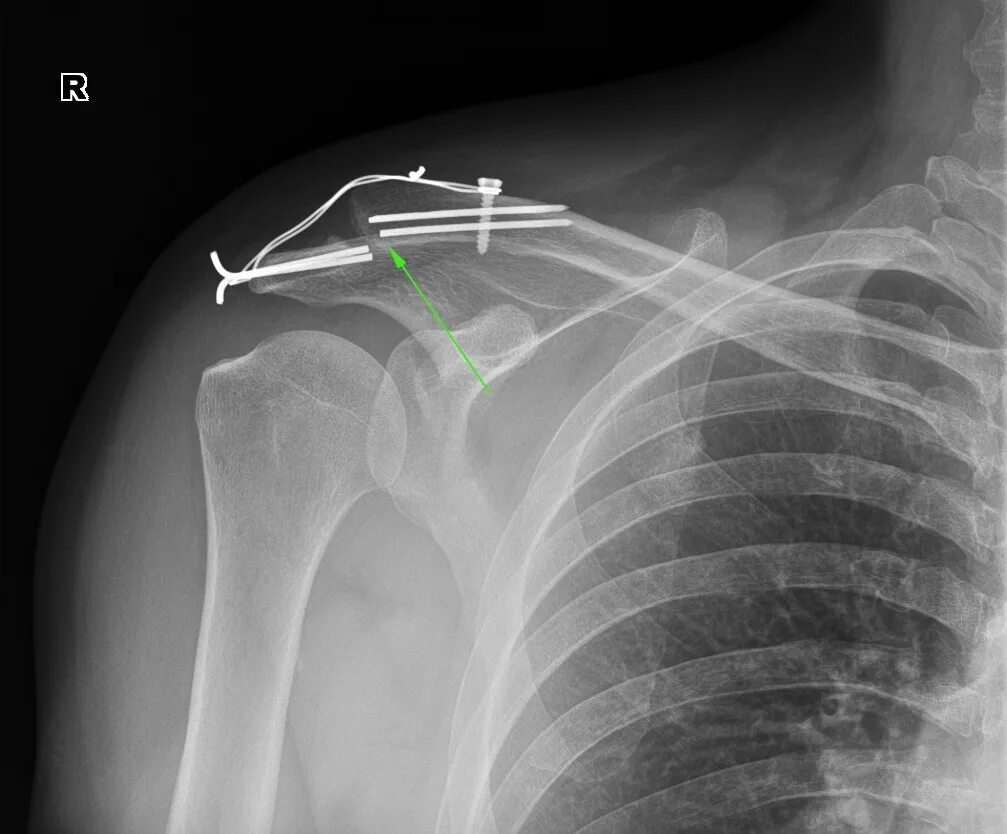

Частичный отрыв